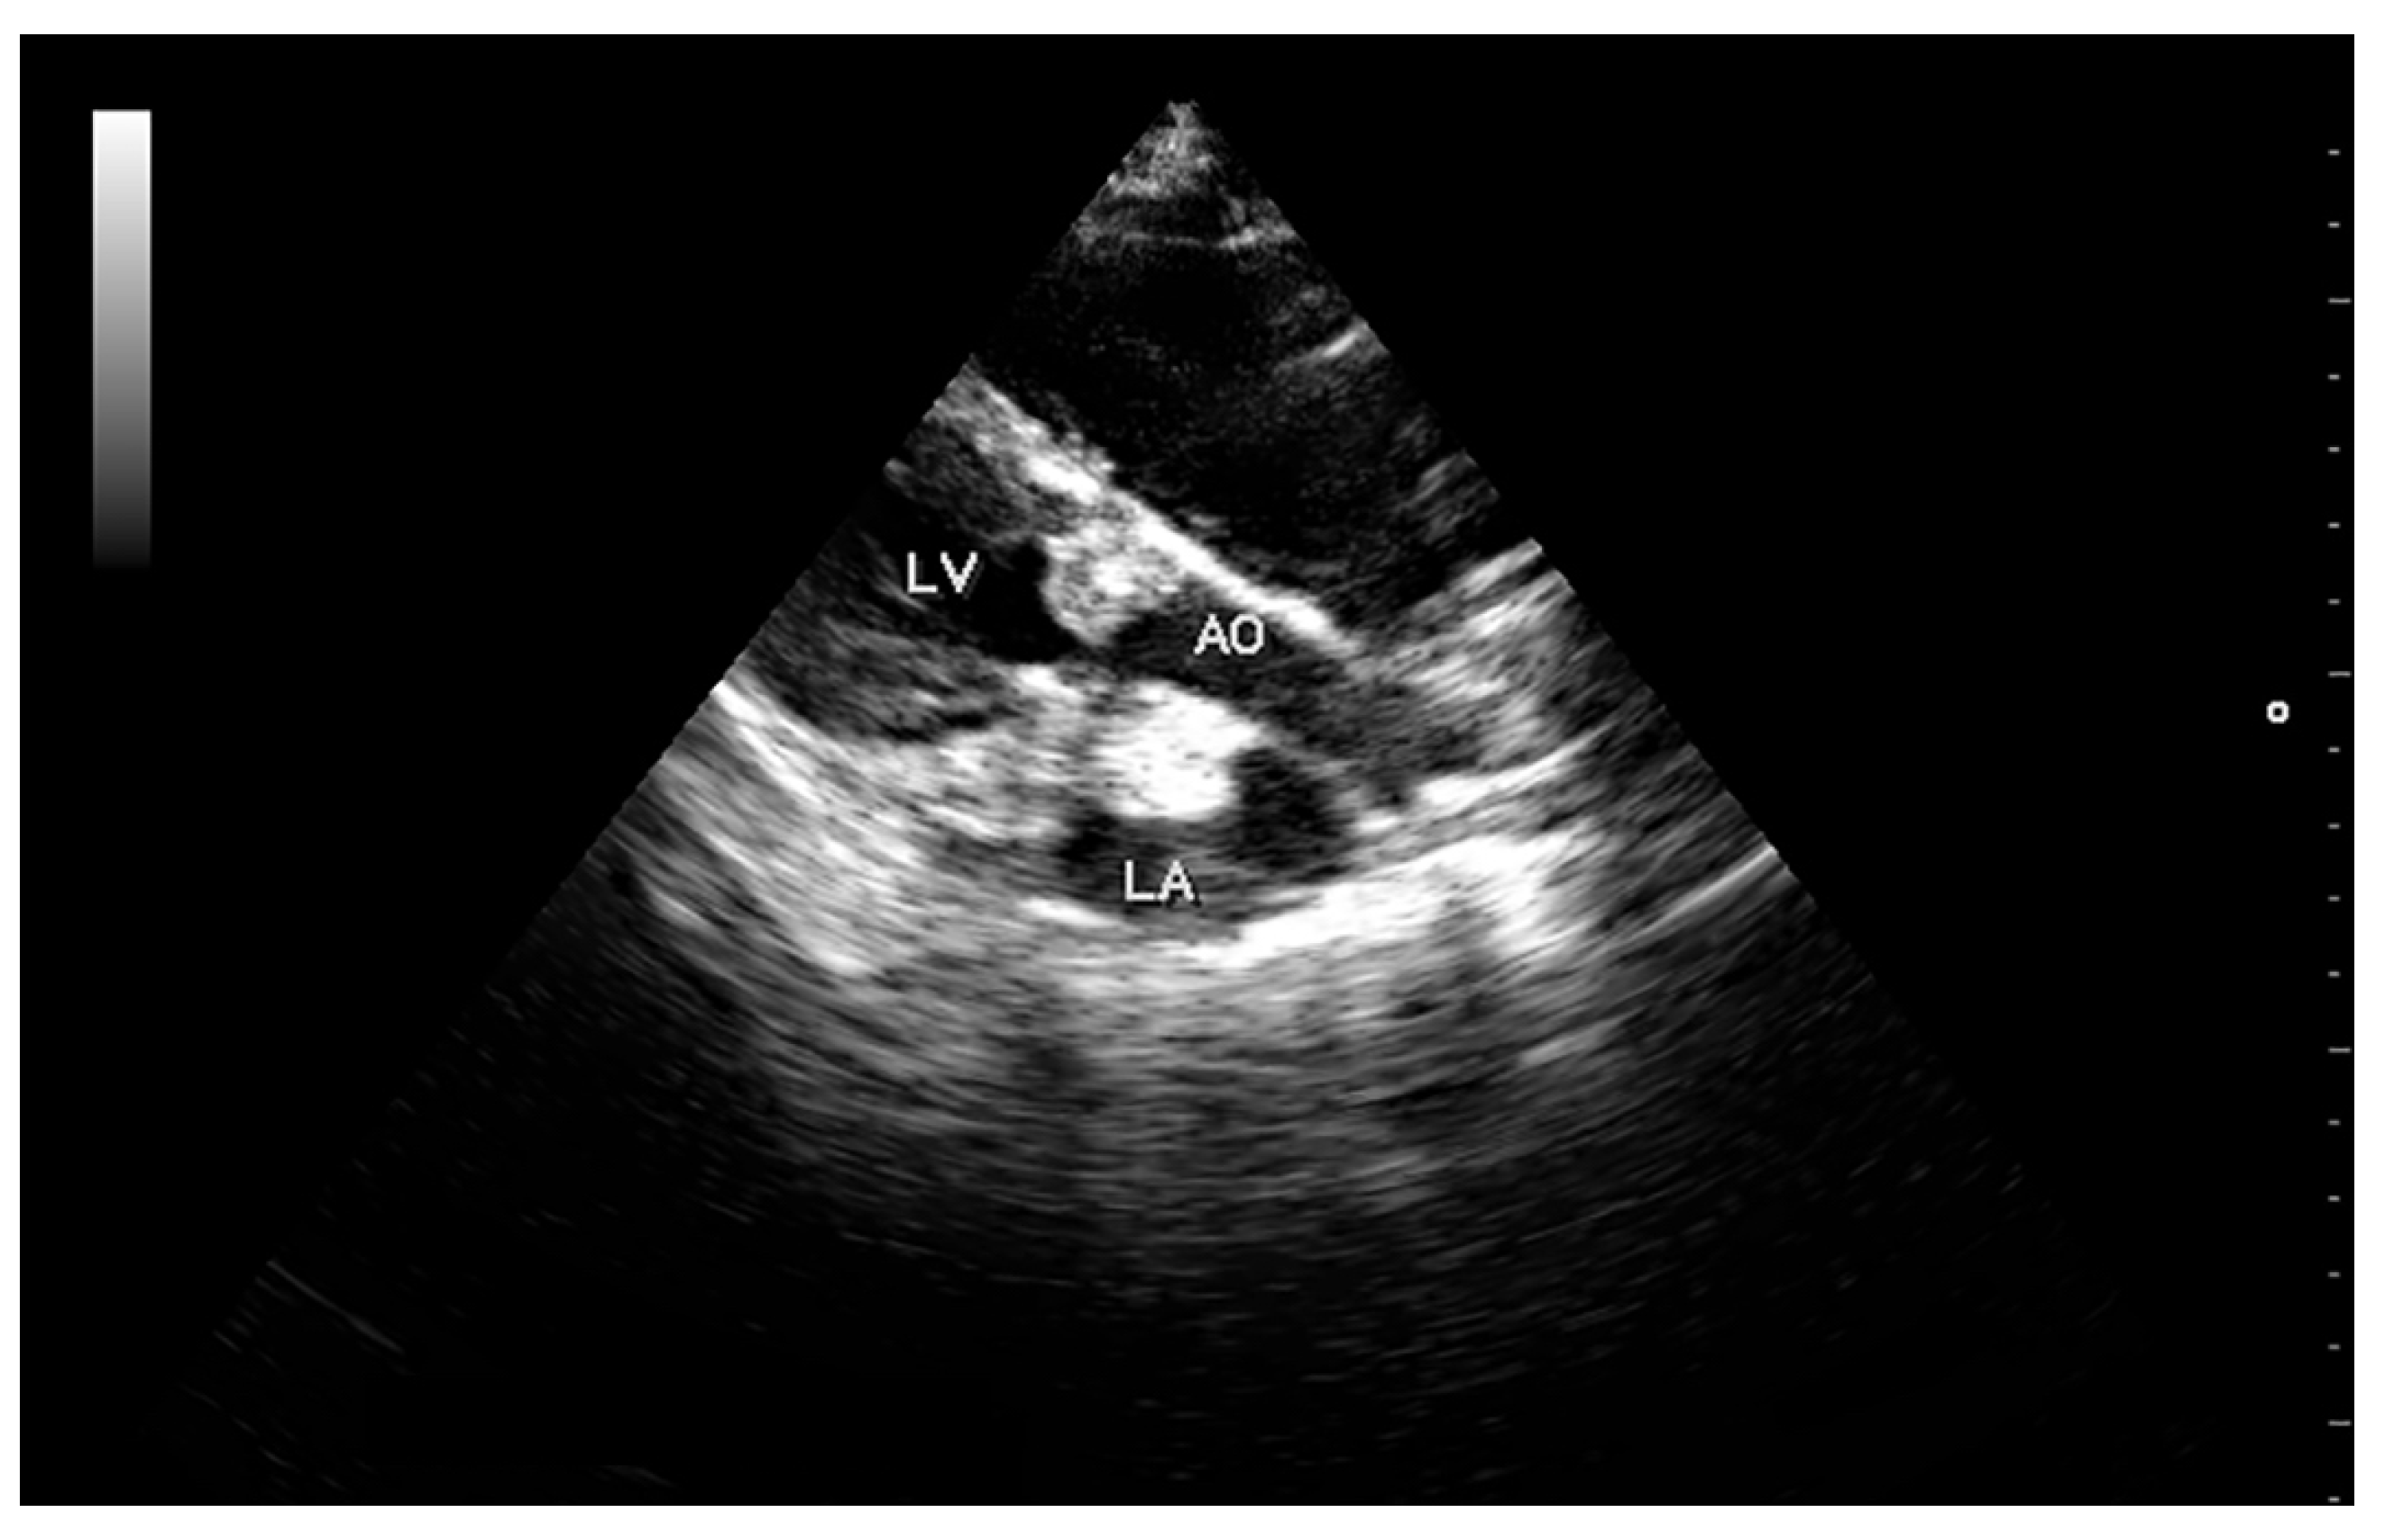

High-resolution images in B and M-mode were obtained (Mylab 30TM, Esaote North America, Inc., Indianapolis, Indiana). The trans-thoracic echocardiogram showed a 1.5 cm vegetative growth on the mitral valve, which was protruding into the left atrium right above the septal cusp of the mitral valve. The mitral valve leaflets were hyperechogenic and thickened (Figure 1). In addition, one of the aortic valve leaflets (the left coronary cusp) was markedly thickened, presenting a 0.6 cm vegetative growth over the body and tip of the leaflet (Figure 2). The affected aortic valve leaflet had a markedly decreased range of motion during systole. However, this cusp was prolapsing into the left ventricle (LV) during diastole, causing it to “kiss” the septal mitral valve cusp (Video I: available in Supplemental Material, online). Severe mitral and tricuspid regurgitation were also observed from the left and right parasternal views, respectively. The location of the regurgitation jets, as well as the aortic flow, were verified using colour Doppler, until a flow signal with a maximum spectral representation of high velocities was obtained. The peak velocity of the aortic flow was 2.9 m/s (estimated peak pressure gradient was 31.3 mmHg). Due to the abnormal appearance of the aortic valve, the hypomotility of the affected cusp during systole, and the abnormal peak pressure gradient, mild acquired aortic stenosis was diagnosed.

Figure 2. Right parasternal longitudinal view of the left ventricular outflow tract showing large vegetations over an aortic valve cusp and above the mitral valve protruding into the left atrium. Abbreviations: LV, left ventricle; AO, aorta; LA, left atrium.

The following are available online at https://www.mdpi.com/2306-7381/5/3/64/s1, Video S1: Left parasternal longitudinal view showing an aortic valve cusp with a vegetative growth prolapsing into the left ventricle during diastole and making contact with a mitral valve cusp (Mitral kissing vegetation).